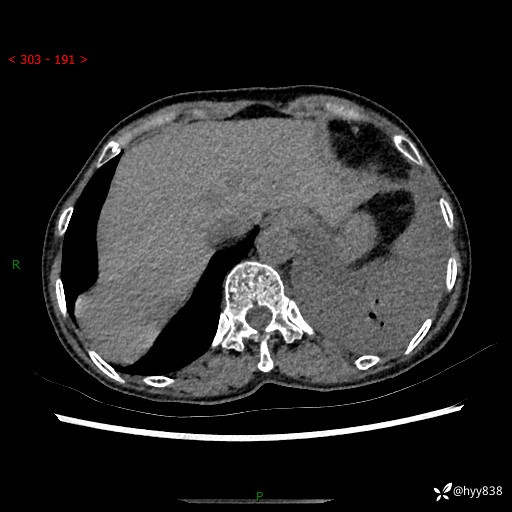

胸部CT平扫+增强